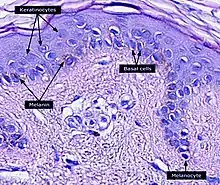

The melanin in the skin is produced by melanocytes, which are found in the basal layer of the epidermis. Although, in general, human beings possess a similar concentration of melanocytes in their skin, the melanocytes in some individuals and ethnic groups produce variable amounts of melanin. Some humans have very little or no melanin synthesis in their bodies, a condition known as albinism.[19]

Melanocytes insert granules of melanin into specialized cellular vesicles called melanosomes. These are then transferred into the keratinocyte cells of the human epidermis. The melanosomes in each recipient cell accumulate atop the cell nucleus, where they protect the nuclear DNA from mutations caused by the ionizing radiation of the sun's ultraviolet rays. In general, people whose ancestors lived for long periods in the regions of the globe near the equator have larger quantities of eumelanin in their skins. This makes their skins brown or black and protects them against high levels of exposure to the sun, which more frequently result in melanomas in lighter-skinned people.[65]